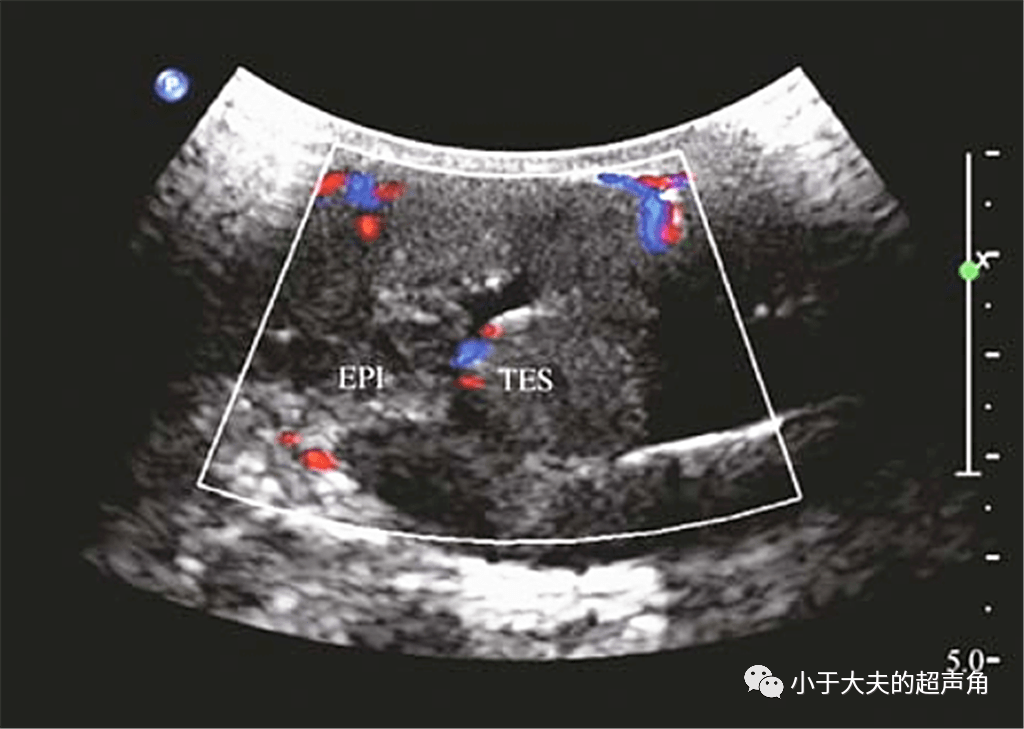

揭秘纤维性假瘤fibrouspseudotumor

图片尺寸1024x729